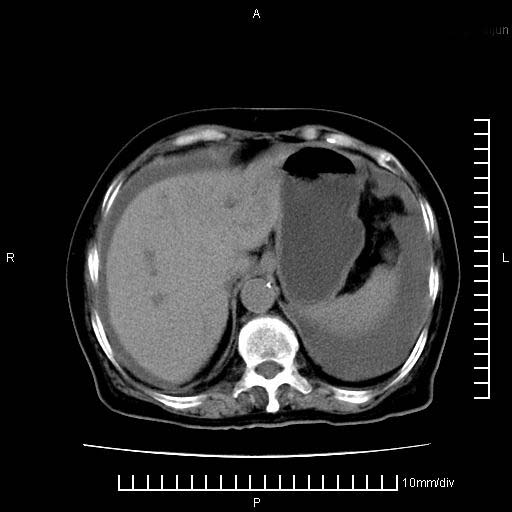

2。肝左叶低密度灶,考虑转移可能

支持胰腺癌肝内转移,腹水改变。

1、考虑胰腺癌伴腹膜腔转移,胸腹水。

2、肝脏转移可能。

考虑胰腺ca伴腹膜腔转移、肝左叶转移、右肾积水。右胸腔积液。